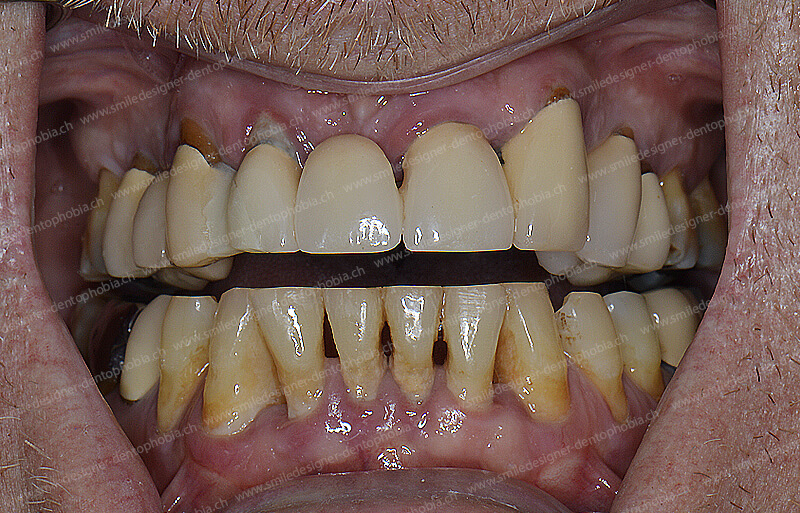

Cas clinique « GOLD STANDARD MCI » maxillaire : Bridge implanto-porté sans extension (ALL ON 8). Version définitive des bridges avec un cosmétique en céramique.

Cas clinique « GOLD STANDARD MCI » maxillaire : Bridge implanto-porté sans extension (ALL ON 10). Version définitive des bridges avec un cosmétique en céramique.